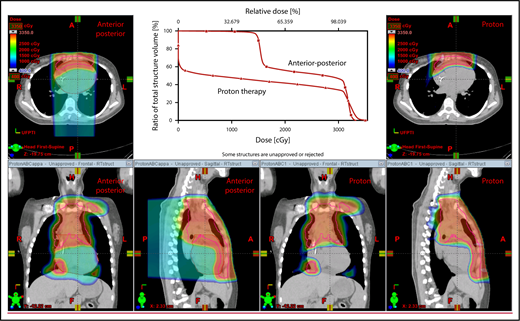

With regard to field arrangements, the PBSPT technique for an anterior upper mediastinal and lower neck target usually requires 1 (repainted) or 2 anterior fields. For more complex target volumes, targets can be divided into 2 or more parts (eg, neck CTV, mediastinal CTV, and axillary CTV), and a multifield plan can be used (Figure 5). For cases that involve lower (posterior) and upper (anterior) mediastinal targets, a combination of posterior and anterior fields can maximally spare the heart and lungs (Figure 6). For upper neck targets, lateral or posterior fields can avoid the oral cavity/salivary structures. For axillary targets, a posterior field can help to spare breast tissue. Although these various field arrangements can be used in PSPT, gradient matching is simpler in PBSPT when the fields overlap or oppose, obviating the need for feathering.

Plans for PBSPT with a single-field uniform dose and a gradient match, with anterior and posterior beams used to treat disease that involves the bilateral upper neck and the mediastinum (disease anterior to the right heart).

Scans for a young woman in whom the target included mediastinal, left parasternal, and left axillary regions. One anterior field was used for the mediastinum, and a separate posterior field was used for the axillary region.